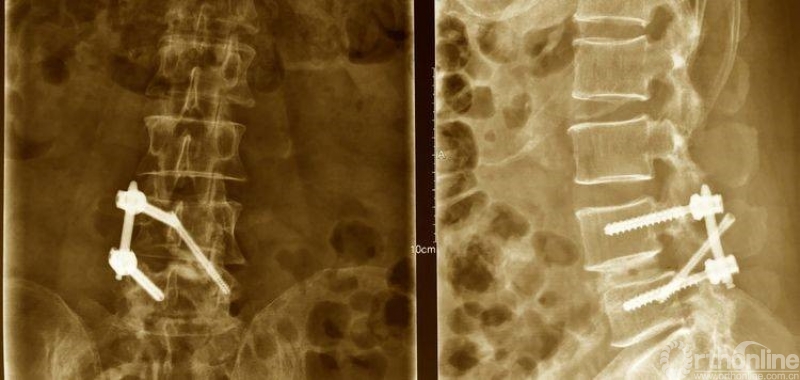

患者术后充分止血后,进行缝合切口、皮肤缝合。整个手术过程耗时2小时45分钟,出血量在50-100毫升,术后不放置引流管,手术顺利。

患者术后定制腰椎支具固定,24小时后下床活动、给予脱水和营养神经药物促进水肿消退,并床上活动锻炼。术后三天复查腰椎CT和平片,术后三天出院。

术后资料:

术后正、侧位片

植入钉棒位置较为合理

椎管狭窄减压较术前容积扩大

矢状位融合器、植骨位置及滑脱复位情况

术后三维CT资料